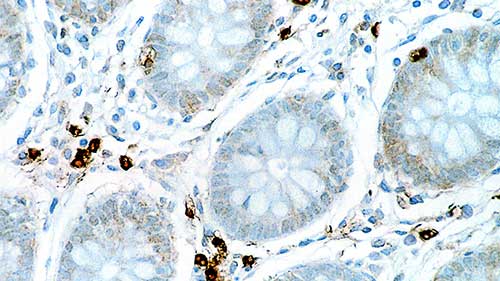

Human colon: immunohistochemical staining for Interleukin 6. Note cytoplasmic staining of a proportion of lymphoid cells. Interleukin 6: clone 10C12

IL-6 is a multifunctional cytokine that is secreted by both lymphoid and non-lymphoid cells. It plays a key role in immune responses, hematopoiesis and is an important cytokine in cell proliferation and differentiation. It may also play an important role as an autocrine growth factor in metastatic prostate cancer. IL-6 has been reported to play a role in secretion or release of pituitary hormone in pituitary hormone secreting cells and adenomas. In addition, IL-6 has been suggested to have a trophic effect in nerve cells and to have a direct pathogenic role in CNS disorders. There are an increasing number of reports that cytokines of the IL-6 family play an important regulatory role in heart physiology.